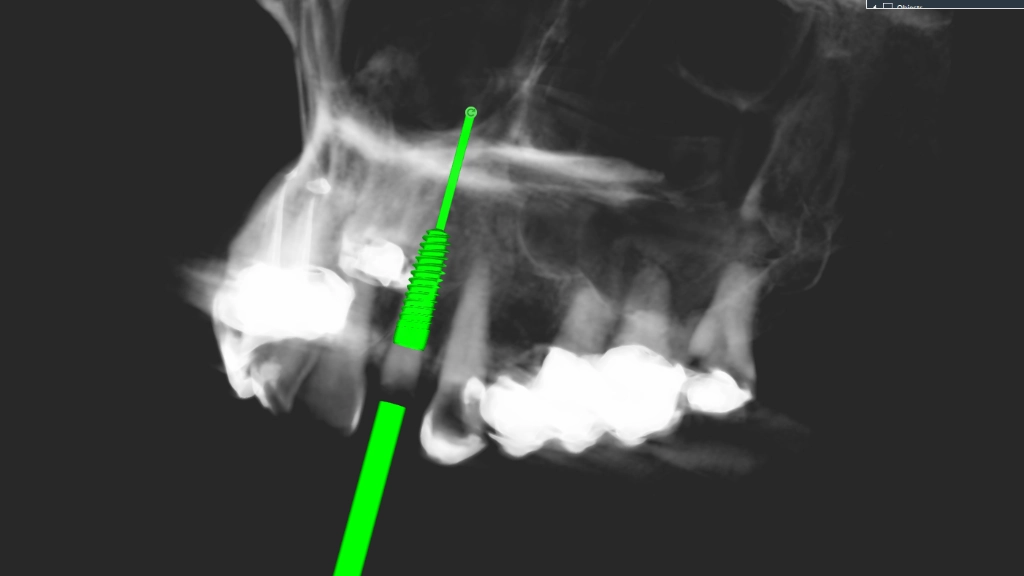

We maken een CT scan van je gebit, een gebitsscan met een soort cameraatje en dan gaat Hurx aan de slag: buiten de mond. In een simulatieprogramma maken we een waxup model, een fictieve planning implantaat en als alles meezit een guide. Een waxup model is een inschatting hoe de nieuwe tand eruit moet komen te zien, we kunnen de implantaatpositie daarop aanpassen.

De röntgenbeelden worden met dit model en de waxup samengevoegd: de positie, implantaatlengte en -breedte worden bepaald:

Daarna wordt een zogenaamde guide ontworpen. Dit is een malletje die tijdens het implanteren exact passend over het gebit geschoven wordt, net als een beugel. In dat malletje is de exacte richting en diepte bepaald. Wij beschikken over een professionele, nauwkeurige 3D printer: het ontwerp wordt werkelijkheid.